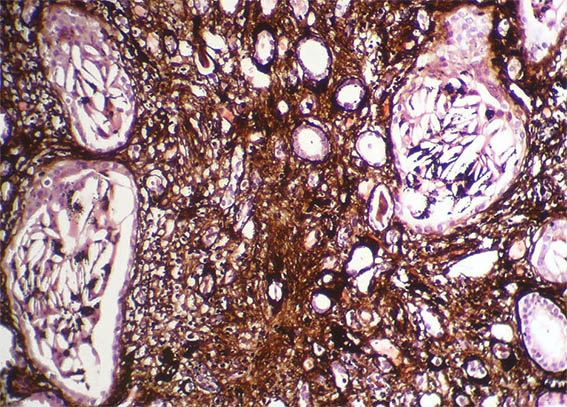

Figura 4. H&E, X100.

Figura 5. Tricrómico de Masson, X100. Observe lo que hay en algunos túbulos, los cuales están muy dilatados.

Figura 6. Plata-metenamina, X200.